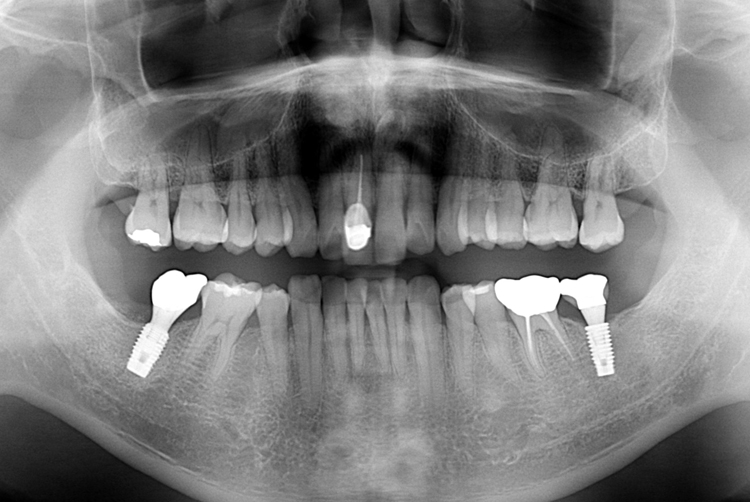

[임플란트] 어금니 임플란트

치료후 : 2017-07-27

세종치과는 많은 환자와 다양한 케이스를 바탕으로

항상 편안한 임플란트 수술을 제공하고자 노력하고,

오래동안 튼튼히 쓸 수 있는 임플란트 수술을 가장 큰 목표로 삼고 있습니다.